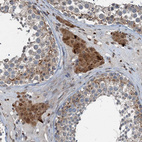

Immunohistochemical staining of human fallopian tube shows moderate cytoplasmic positivity in glandular cells.